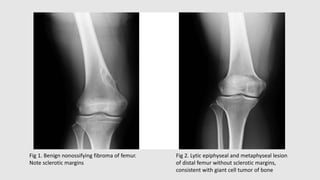

Dense sclerotic margin around the tumor is a characteristic sign of a benign tumor of bone

(Fig. 1).

Lack of sclerotic rim suggests more rapid growth of the underlying lesion (Fig. 2).

Fig 1. Benign nonossifying fibroma of femur.

Note sclerotic margins

Fig 2. Lytic epiphyseal and metaphyseal lesion

of distal femur without sclerotic margins,

consistent with giant cell tumor of bone